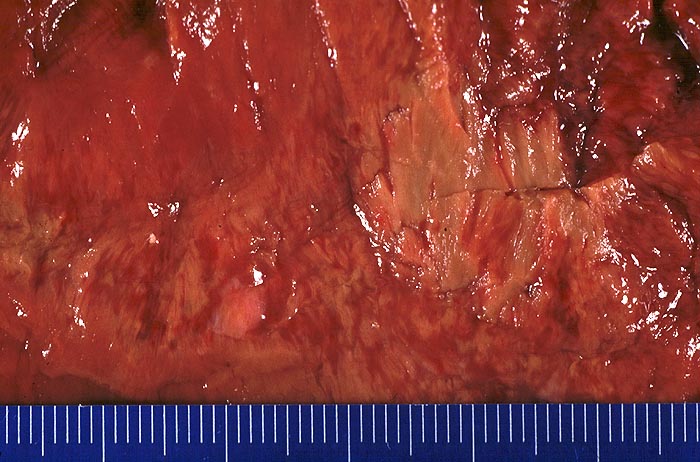

Subakuter Myokardinfarkt

Blick auf die Schnittfläche der linken Herzkammer. In der Mitte ist das lehmgelbe leicht erhabene Nekroseareal erkennbar. Dieses wird umgeben von einem breiten Granulationsgewebssaum. Das Granulationsgewebe baut von aussen her die Nekrosezone ab und hat aufgrund seines Gefässreichtums eine rote Farbe.

Mehrere Tage alter Infarkt.